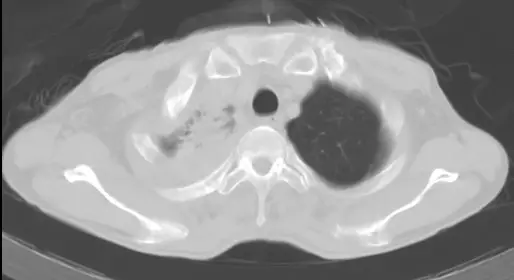

51 歲男性病患,因為近半年來右上背酸痛和右上肢麻痹和無力到院就醫。他因這些病症在他院接受止痛藥物治療和手術治療頸椎椎間盤突出開刀,但症狀未見改善。到院前三個月,他開始出現右眼皮下垂和視力模糊。他過去抽菸,一天一包達三十年之久。到院胸部 X光和電腦斷層檢查如圖。多次痰液微生物顯微鏡檢和培養均為陰性。以下何者是最有可能的診斷? 圖片 圖片

影像二:胸部電腦斷層(CT,軸向切面)

CT 軸向切面顯示右側肺尖可見一不規則軟組織腫塊(soft tissue mass),腫塊位於右側 superior sulcus 區域,緊鄰胸壁及縱膈。腫塊邊緣不規整,與周圍脂肪平面界線模糊,提示有胸壁侵犯(chest wall invasion)。左側肺野清晰,縱膈無明顯淋巴結腫大。此 CT 發現與 Pancoast 腫瘤的典型影像表現吻合:位於肺尖的不規則軟組織腫塊,